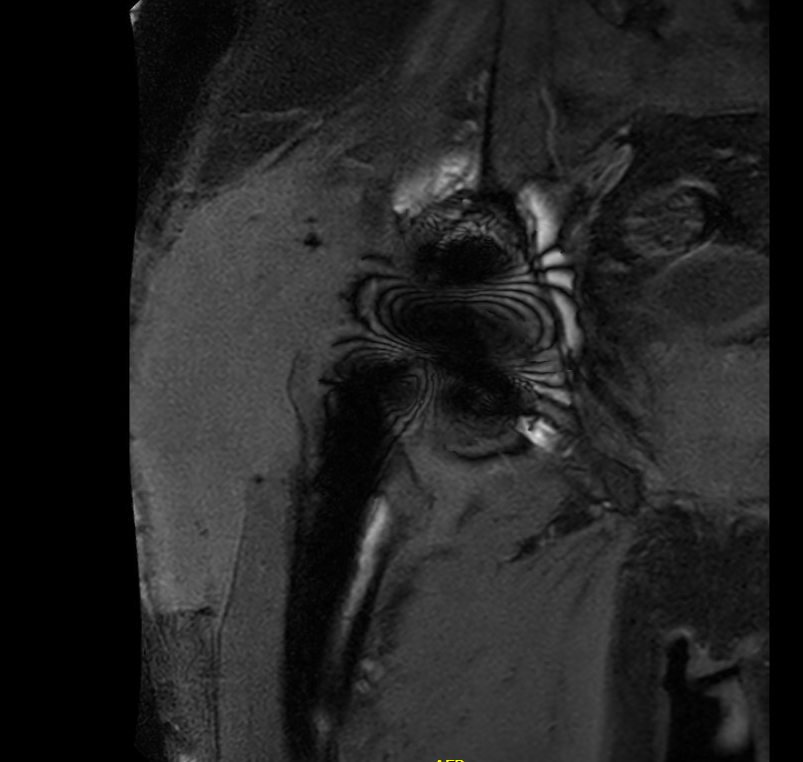

MRI / CT

MRI demonstrating large fluid collection around THA